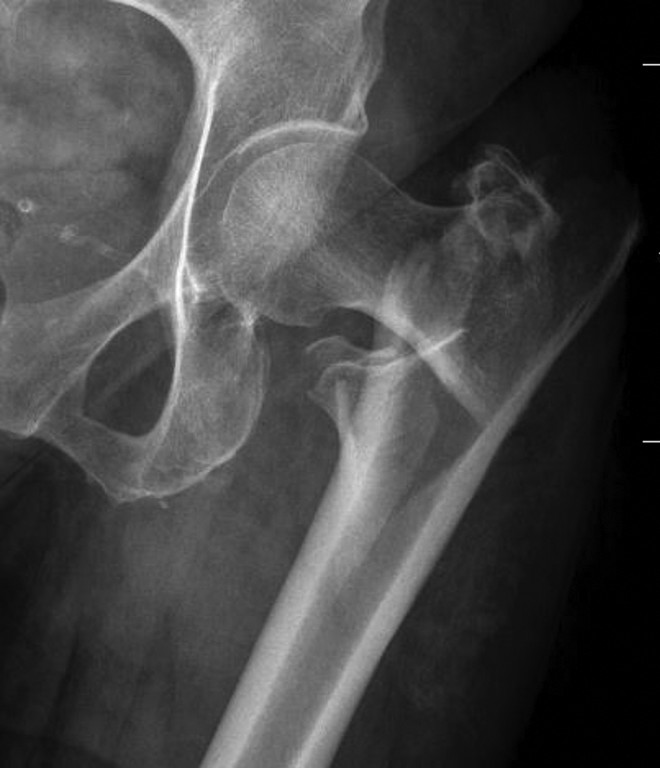

植入物的选择主要取决于骨折的稳定性和外侧皮质的完整性。稳定型股骨粗隆间骨折通常具有完整或复位良好的后内侧皮质支撑(图6),这样可以帮助股骨近端分布应力并承受内侧压力。与此不同,不稳定型骨折在使用髓外固定时往往难以保持股骨近端的复位。这类骨折通常包括:因粉碎或大块骨折块损伤的内侧股骨距,延伸至转子下区域的骨折,反斜形骨折,或是涉及外侧皮质的经转子骨折。(图7-10)

图6. 股骨粗隆间稳定型骨折X光片(AO/OTA分型 31-A1)。注意内侧股骨距区域无粉碎性骨块。

图7. 左髋X光片显示不稳定的股骨粗隆间伴有分离的后内侧骨折块(AO/OTA 31-A2)。